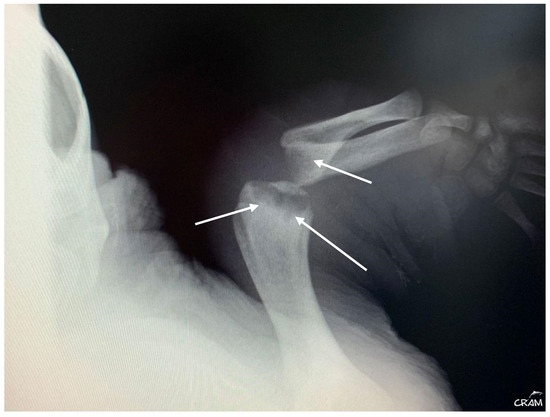

In December 2020, CC20/051 suffered a bycatch incident by a trawler ship. At the rescue center, it was diagnosed with pneumonia by radiography (Figure 3) and started treatment with ceftazidime 22 mg kg−1, SC q 72 h for 15 days. In January 2021, the turtle was released.

Figure 3. Radiographic examinations in cranio-caudal (a) and lateral (b) projections of the lungs. The images show an opacification of the whole parenchyma following bacterial pneumonia. The arrows show a densification of the peribronchial lung parenchyma.